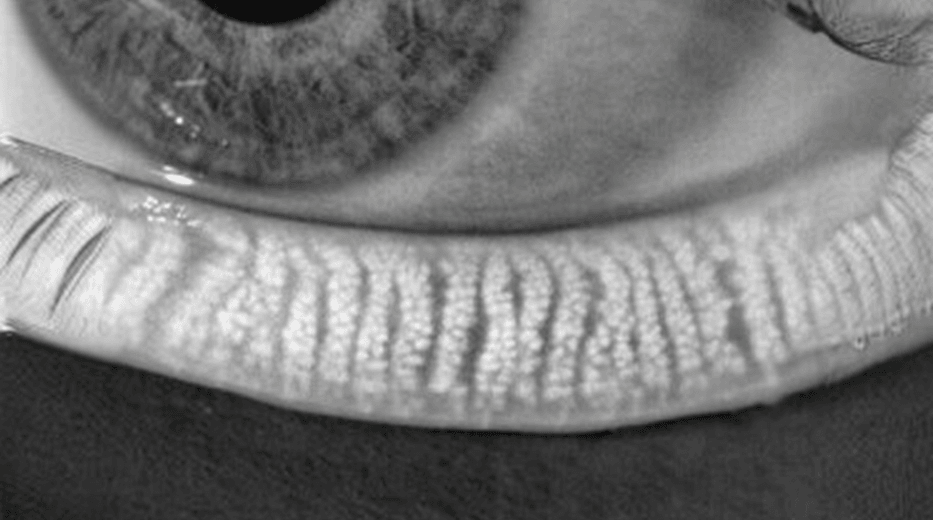

Meibomian Gland Dysfunction (MGD) Assessment

Meibomian Gland Dysfunction (MGD) can be

thoroughly assessed through precision diagnostics

MGD is a chronic, progressive,

and obstructive condition.

Maintaining the healthy function and structure of the meibomian glands

before dry eye symptoms appear is crucial.